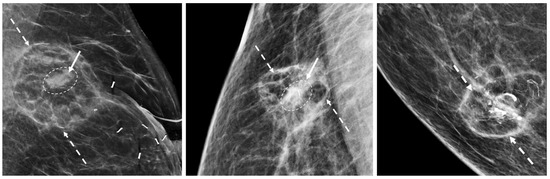

The mammographic appearance of the cryoablation site is typically characterized by a thin, spherical scar or cryoball that roughly corresponds to the dimensions of the iceball that was achieved at the time of cryoablation or to the dimensions of the cryoablation zone of inflammation that was ultimately achieved. The “eggshell” appearance of the cryoball is more apparent in fatty breasts but more subtle in dense breasts (Figure 20) [43]. Another common post-cryoablation mammographic feature is the persistence of a tumor “ghost,” which is the visible remnant of the necrotic cancer mass that gradually resorbs over time. Although the tumor ghost is expected to gradually disappear, microcalcifications associated with the malignancy are expected to persist even when the surrounding cancer cells have been completely resorbed. Microcalcifications are essentially fossilized remnants of dead cancer cells that have become calcified and petrified, and as such are not digestible by the immune cells. However, it is possible for new microcalcifications to appear. Most often, new microcalcifications or macrocalcifications within or adjacent to the cryoablation site indicate the development of benign fat necrosis (Figure 21), a common manifestation of tissue trauma. It is also possible that new microcalcifications within or adjacent to the cryoball could indicate the presence of recurrent disease. In either case, a stereotactic or mammographic guided needle biopsy might be needed to distinguish between recurrence and fat necrosis.

Figure 20.

Post-cryoablation mammograms showing thin walled, spherical scars or cryoballs (broken arrows) and centrally located tumor ghosts (indicated by solid arrows and encircled with hash marks).